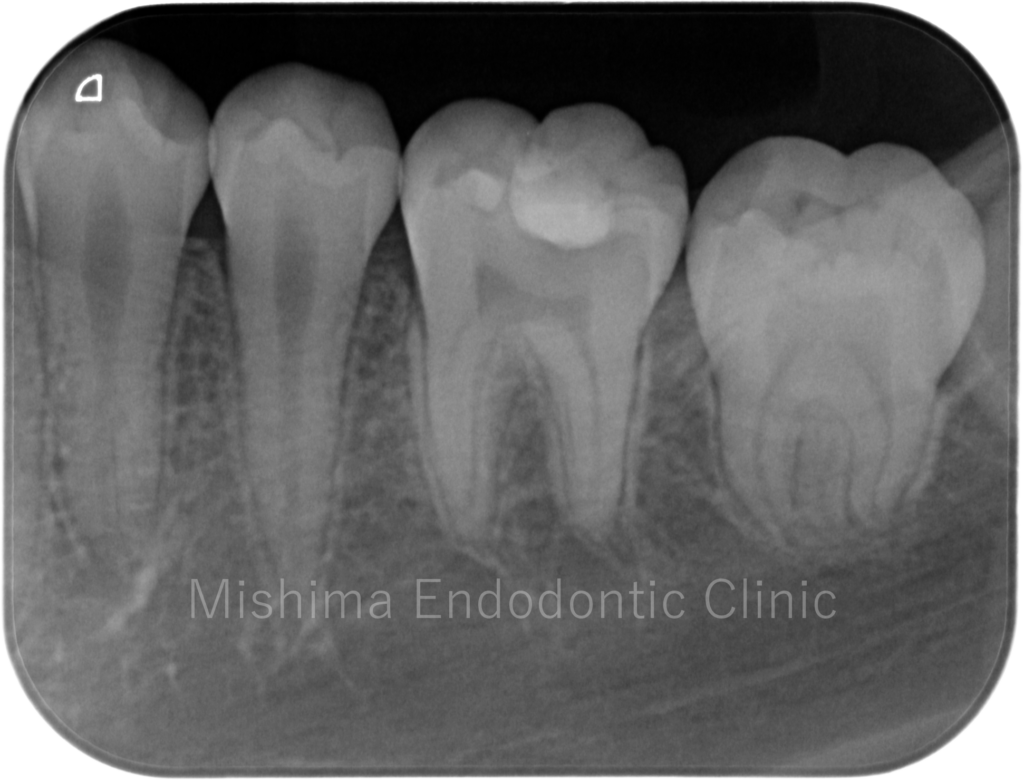

Before

| 治療内容 | 咬合面にCRにて修復されており、CR下にてカリエスを認めた。歯髄診査にて歯髄は正常歯髄と診断。カリエスを除去していくと露髄を認め、壊死歯髄を除去、部分断髄し、バイオデンティンにて覆髄、CRにて最終修復まで行った。 |

術前